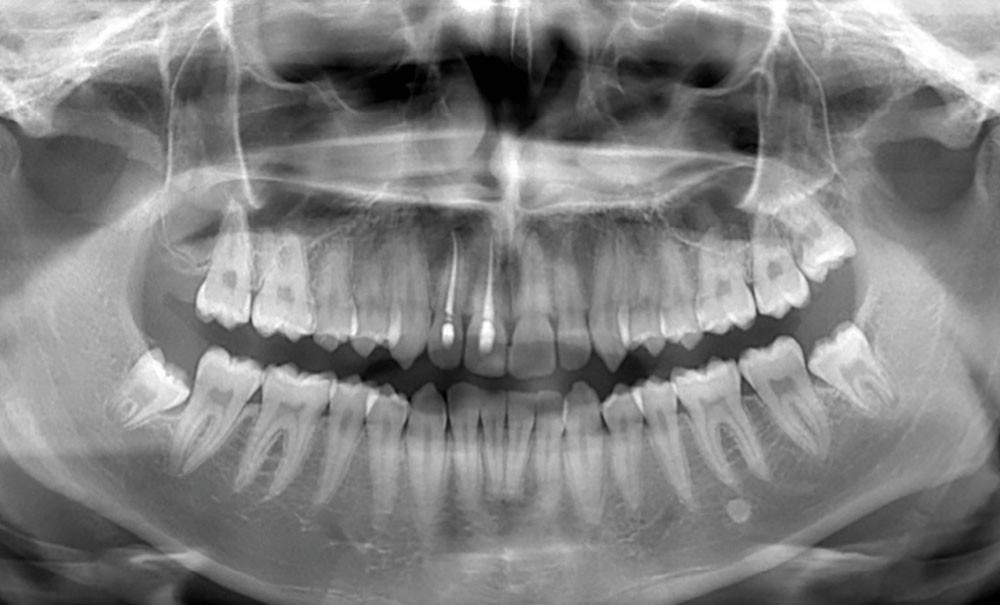

QUIZ 2

Contexte clinique Quiz 2

Réalisation d’une radiographie panoramique chez un patient âgé de 62 ans, sans/avec symptomatologie douloureuse.

- Quelle anomalie radiologique observez-vous sur cette radiographie panoramique ?

- Comment la nommeriez-vous ?

- Quels diagnostics différentiels pourraient être évoqués ?

- Quels examens complémentaires et/ou quelle conduite à tenir recommanderiez-vous…